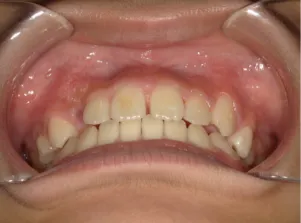

治療前①小5:スタート

| はじめのご相談 | 凸凹になりそうと一般歯科の先生に言われたのでみてほしい |

|---|---|

| カウンセリング・診断結果 | 下あごが後退しているタイプの出っ歯で、過蓋咬合で下あごが前に成長しにくいタイプの顔立ちです。 上の歯列弓が小さめで前歯に凸凹があります。 口元が閉じにくい口唇閉鎖不全があります。 *上記に対する治療の流れを説明し(拡大・前歯の並べ替え→出っ歯の改善→モノブロック装置(筋機能的咬合誘導装置)→必要によりマルチブラケット法)、以下の治療を提案しました。 |

| 行ったご提案・診断内容 | 成長期に行う治療と咬合治療をご提案しました。 成長期治療(成長時期にお口の環境を整え、適正な成長を促す治療)で、 ①歯列弓形態の修正、拡大と前歯を並べる。 ②出っ歯を治す専用の装置を使用する。 ③・MFT:舌や口唇などが正しい動きやポジショニングで機能し、鼻で呼吸できるようにする練習、毎日おうちで習慣づくように続けてもらいます。 ④拡大による顎顔面の適正な成長効果で口元を改善する(写真③)。 |